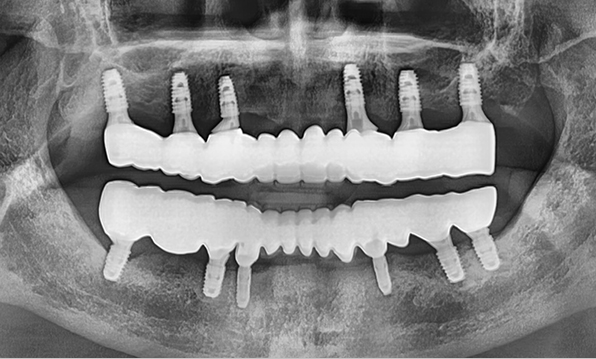

In full-mouth implant cases, implants are placed only where needed, and the remaining gaps are restored using a bridge (pontic) method — minimizing the total number of implants while achieving masticatory force comparable to natural teeth, helping to reduce the financial burden.

Bridge-type implant

Before & After

Case 02

Before After